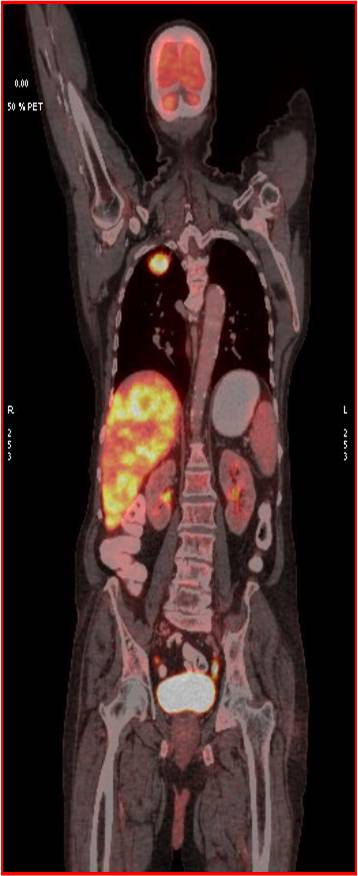

CT scan of the abdomen confirmed the findings ; For further clarification PET whole body scan was done at a centre in Chennai. The following images are from that.

- Metabolically active spiculated right upper lobe lung mass – likely malignant primary.

Mediastinal and retroperitoneal FDG avid metastatic lymphadenopathy.

Extensive FDG avid hepatic metastases involving both lobes.

Focal FDG avid lesion in left lamina of D10 – possibly metastatic.